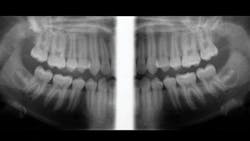

Although the exact percentage of general dentists removing impacted teeth is unknown, various surveys have reported this number as high as 50%. When removing an impacted third molar, it is highly desirable to know the exact location of the roots, their angulation, their proximity to the maxillary sinus or the inferior alveolar canal, and other characteristics. A panoramic image really helps, but a cone-beam image is even more helpful (figure 3). Having access to a cone-beam image of impacted teeth gives the clinician a higher level of understanding of the surgical situation and the apparent difficulties that may be encountered.

Figure 3: Extraoral bitewings made on a cone-beam device showing peculiar lack of development of third molars. Before removal, a cone-beam image is needed to show the exact location of the third molars.